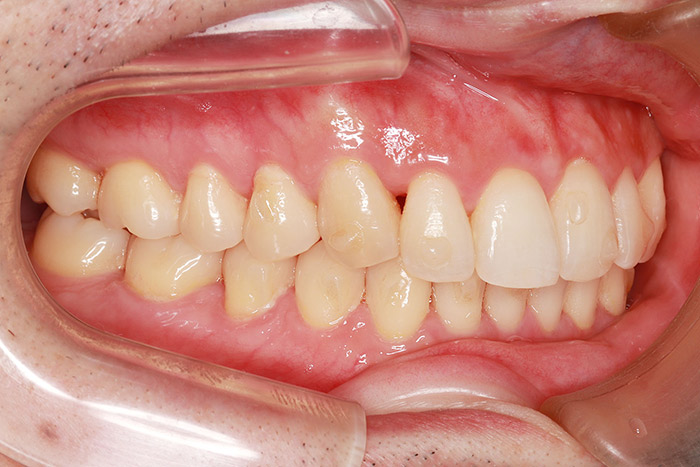

T様

治療前

年齢 28歳

性別 女性

治療名称 唇側ブラケット装置(ワイヤー矯正)

総額治療費用 880,000円(税込10%) 金額備考 精密検査料・診断料 33,000円(税込10%)

治療期間 2年6か月 通院頻度など 1か月ごと

患者の症状 叢生、上下顎前突

治療方法 上下顎小臼歯の4本抜歯して唇側マルチブラケット装置にて矯正

治療結果 叢生の解消、口元の突出感も緩和され咬み合わせが良くなりました。

その他治療に関する情報 装置撤去までの通院回数は23回、その後の保定期間(2年間)は3か月に1度の通院。